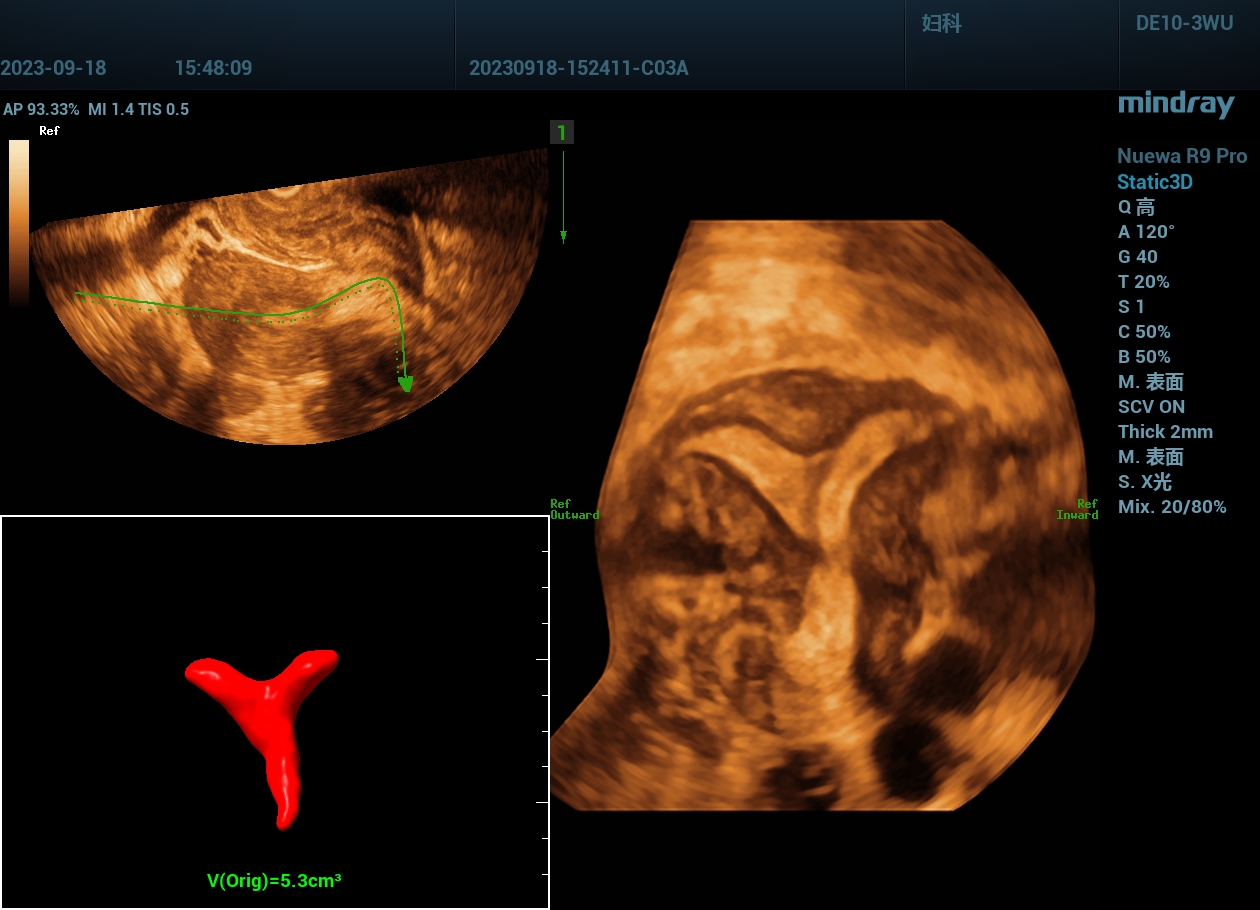

病例,弓形子宫2:宫腔形态异常,二维+三维

www.jinrichaosheng.com